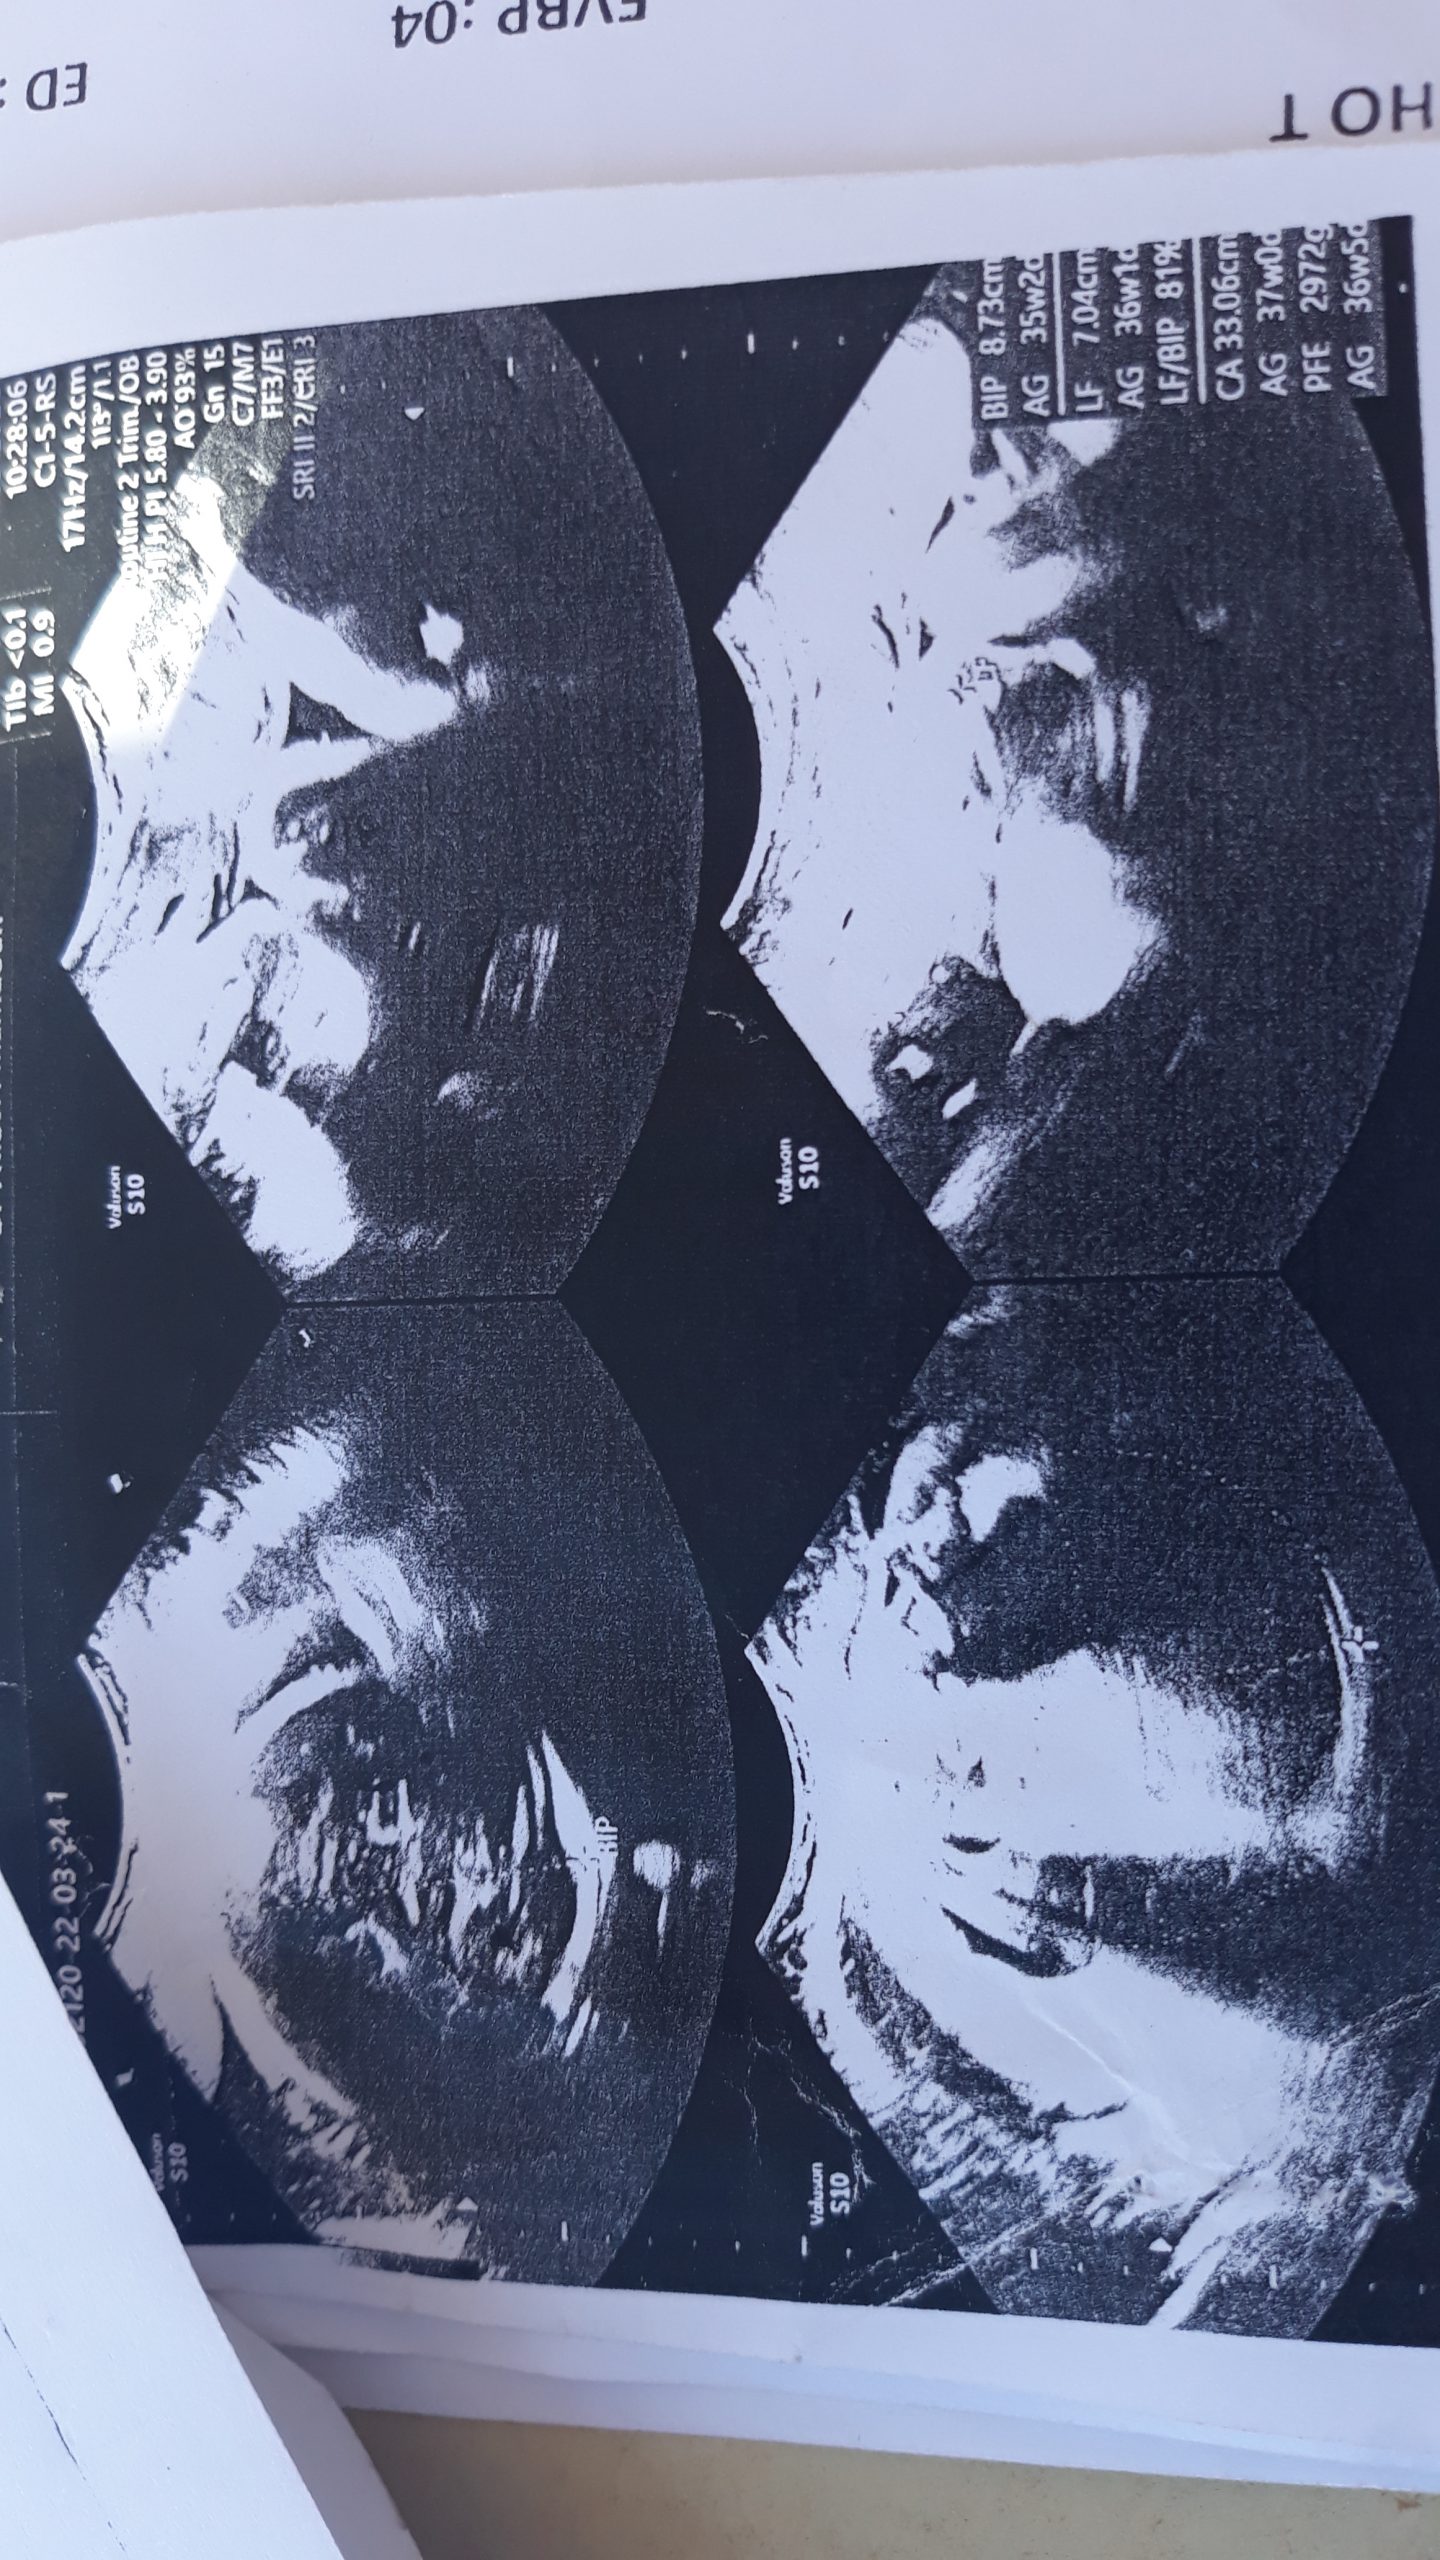

“شامي رقية” والدة الرضيع المختطف، أكدت في حديثها لـ “النهار” أنها ذهبت لعدة أطباء لمتابعة حملها، وكل الأطباء أكدوا أنها حامل بتوأم من جنس ذكر، وعند دخولها للعيادة وملء البيانات وإجراء العملية القيصرية، شاهدت الأم طفلاها وهي على طاولة العمليات، وبعدها نقلت لغرفتها، لتتفاجأ بطفل واحد فقط، لتدخل في حالة “هستيريا” كبيرة، كيف لا والرضيع الثاني والذي تمت تسميته “عبيدة بن الجراح” لا يوجد بجانب أخيه في السرير الذي بجانبها داخل العيادة.

يحدث هذا في انتظار ما ستفسر عنه التحقيقات الأمنية وكذا العدالة الجزائرية المتواصلة لحد الآن، بعد مرور أزيد من 4 أشهر عن الواقعة، فيما ناشدت عائلة “قويسي”، السلطات العليا في البلاد، إيفاد لجنة تحقيق إلى العيادة من أجل إرجاع الطفل إلى ذويه، في ظل توفر كل الإثباتات الطبية بأن الأم “شامي رقية” زوجة “قويسي ماجر” كانت تحمل في بطنها توأما.